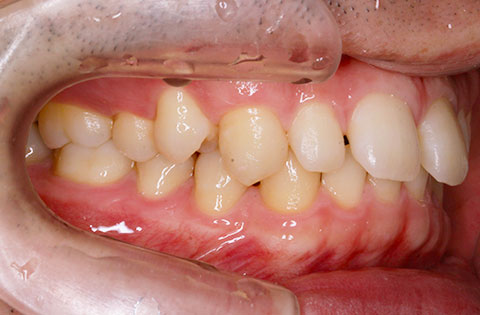

矯正前 右側

矯正後 右側